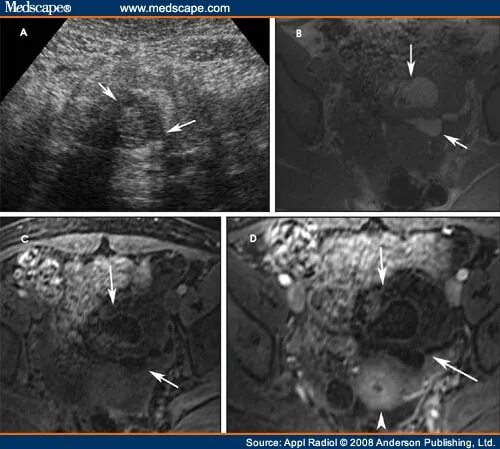

Объемные кистозные образования